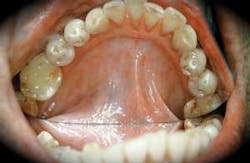

Etiology:Multiple causes are documented for this premalignant condition. The prime cause of the condition is from a combination of products used by the person in the form of betel leaf (which is from the piper betel vine, a relative of the pepper family), tobacco, areca palm (the seed of the area palm), additional spice flavoring additives such as cinnamon, cloves, melon, cucumber seeds and sweets, and slaked lime paste (from chalk, coral, and sea shells). The ingredients are placed directly on a betel leaf and rolled tightly into what is termed a quid. The quid is chewed or held in the mouth for a period of time against the tissues, and in some instances, the patient may even sleep with the quid in place. Other contributors to the etiology of submucous fibrosis are nutritional factors such as vitamin deficiency and a genetic predisposition. The combination of these products and the potency will vary with each user. Individuals who are raised in certain areas of the world may also use betel and areca nut by chewing the product in addition to quid placement or as a separate habit. The way the products are used is determined by ritual as well as cultural practices. In India, catechu is a product that is derived from acacia pods and poor quality areca nuts that are often boiled or roasted in the sun. The mixture is considered especially astringent due to the high concentration of tannin. An added enhancer of the product is the lime preparation which acts to release an alkaloid from the areca nut, producing a feeling of euphoria and well-being. The combination of the products is referred to as pan. See Figure 2.